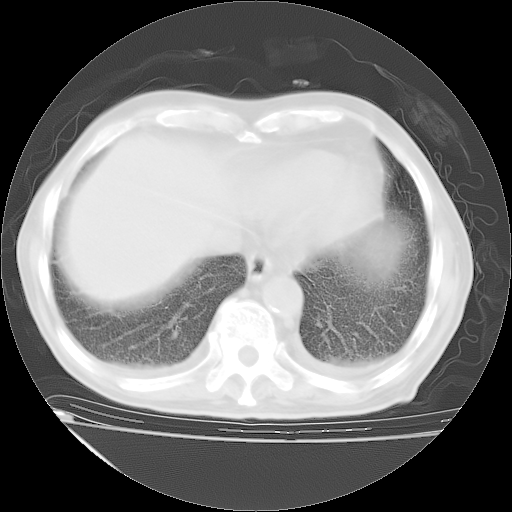

甲强龙80mg/日+抗结核治疗(异烟肼+利福霉素+乙胺丁醇)10天。复查肺部CT。

治疗10天肺部CT

94186 3 10.bmp

94186 3 11.bmp

94186 3 12.bmp

94186 3 13.bmp

94186 3 14.bmp

94186 3 15.bmp

94186 3 16.bmp

94186 3 17.bmp

94186 3 18.bmp

94186 3 19.bmp